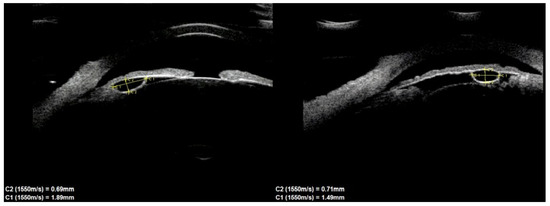

This study evaluated the characteristics and clinical course of patients with iris cysts in the long-term follow-up (24–48 months). We retrospectively analyzed the medical records of 39 patients with iris cysts (27 women and 12 men). Age, visual acuity, intraocular pressure (IOP), slit-lamp [...] Read more.

This study evaluated the characteristics and clinical course of patients with iris cysts in the long-term follow-up (24–48 months). We retrospectively analyzed the medical records of 39 patients with iris cysts (27 women and 12 men). Age, visual acuity, intraocular pressure (IOP), slit-lamp evaluation, and ultrasound biomicroscopy images were assessed. The mean age at diagnosis was 40.6 ± 17.48 years. Thirty (76.9%) cysts were peripheral, five (12.8%) were located at the pupillary margin, two (5.1%) were midzonal, and two (5.1%) were multichamber cysts extending from the periphery to the pupillary margin. A total of 23 (59%) cysts were in the lower temporal quadrant, 11 (28.2%) were in the lower nasal quadrant, and 5 (12.8%) were in the upper nasal quadrant. Cyst size was positively correlated with patient age (rs = 0.38, p = 0.003) and negatively correlated with visual acuity (rs = −0.42, p = 0.014). Cyst growth was not observed. The only complication was an increase in IOP in three (7.7%) patients with multiple cysts. The anatomical location of the cysts cannot differentiate them from solid tumors. The vast majority of cysts are asymptomatic, do not increase in size, and do not require treatment during long-term follow-up. Full article

Show Figures

Figure 1